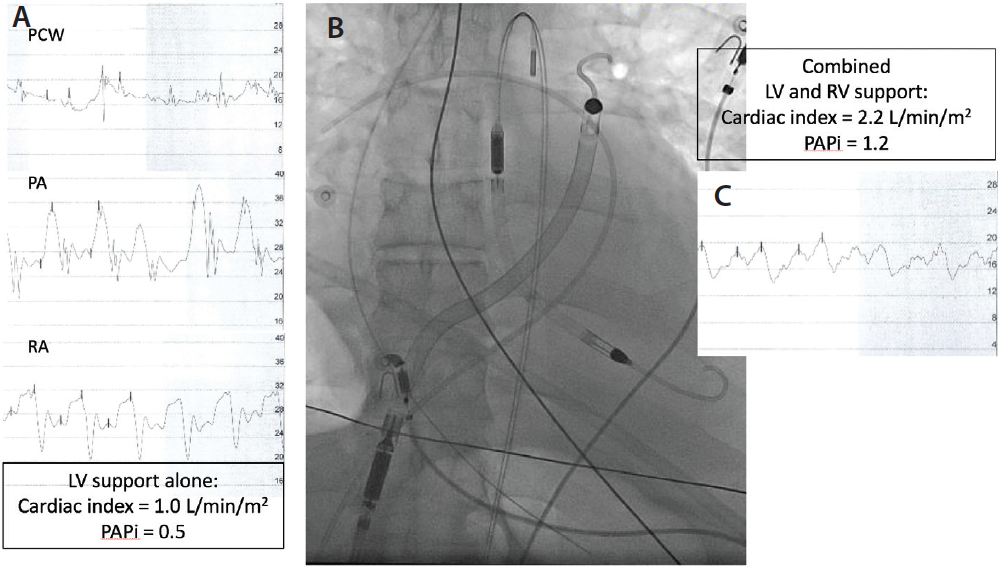

Figure 1. Acute IMI with RVI. Echocardiography reveals RV enlargement with dyskinetic free wall motion and septal bowing toward the relatively underfilled LV. Angiography reveals occlusion of proximal right coronary artery. ED, end diastolic; ES, end systole. Adapted from Bowers TR, O’Neill WO, Pica M, Goldstein JA. Patterns of coronary compromise resulting in acute right ventricular ischemic dysfunction. Circulation. 2002;106:1104–1109.

Acute RV failure may be associated with acute inferior myocardial infarction (IMI) with RV involvement (RVI) (Figure 1), post–LV assist device (LVAD) implantation, postorthotopic heart transplantation, postcardiotomy after any cardiac surgical procedure, acute pulmonary embolism, and acute right heart valve insufficiency (eg, acute tricuspid or pulmonic valve regurgitation). Echocardiography provides evidence of RV failure, including RV dilation, depressed RVFW motion, and diminished RV ejection fraction. The right ventricle may be larger than the left ventricle (RV/LV end-diastolic area ratio > 0.6), and reverse septal curvature is often present.5 Echocardiography is also useful to exclude pericardial disease, which is beyond the scope of this review.